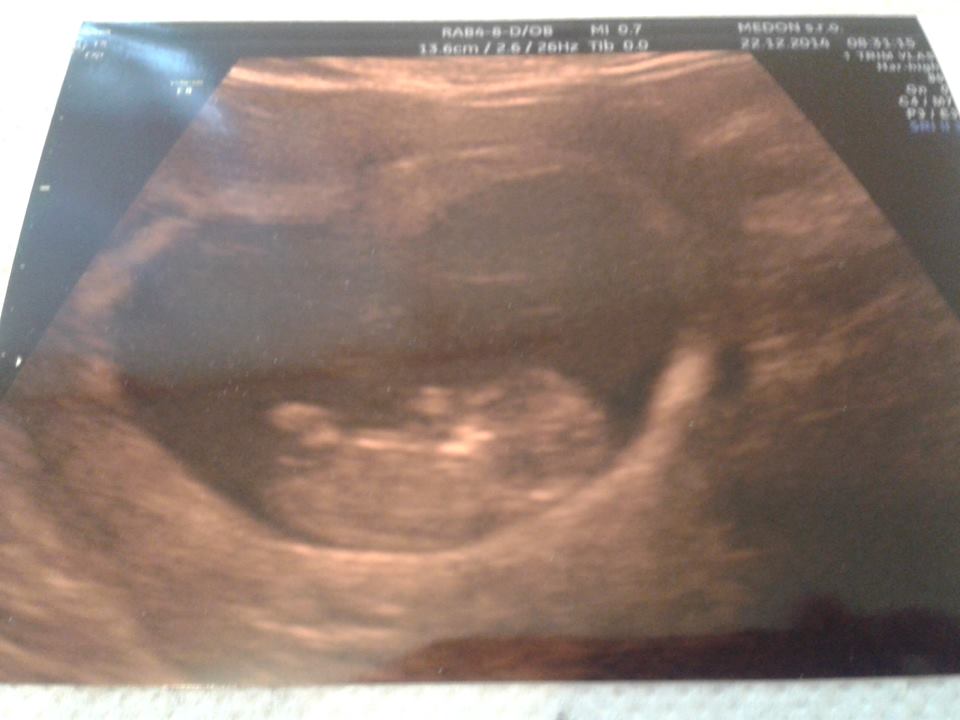

Ked som dorazila, mm ma hned odviezol na pohotovost aby ma vysetrili, a to som tam sla s velmi malou nadejou a dusickou! À le ked mi doki povedal, ze su tam 2, normalne som ani neverila! 😉 A to tu nedavaj vobec ziadne injekcie dokonca nez na SK.... 😒

À le po tyzdni opat kontrola a to uz bolo len jedno bambulko so srdieckom, aspon tak! 🙂